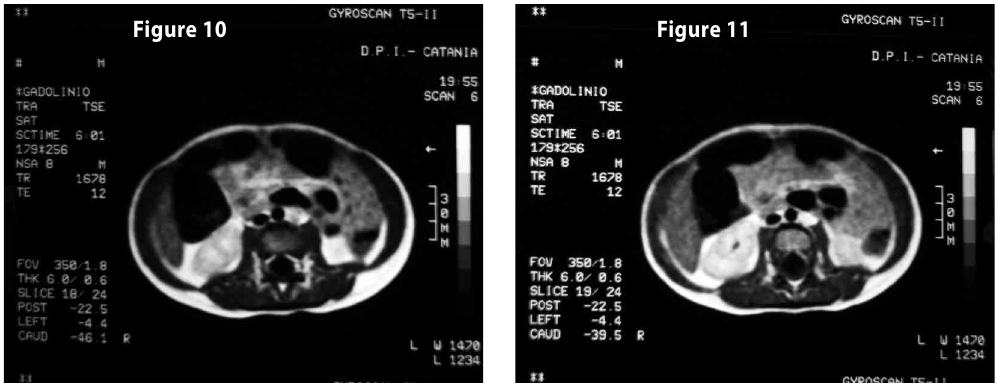

Complete objective response of neuroblastoma to biological treatment.

Figure12-13